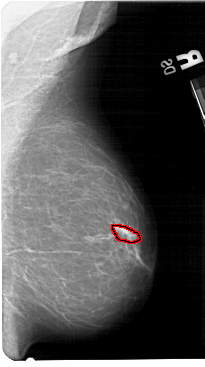

A_1548_1.LEFT_MLO

LEFT_MLO LINES 5491 PIXELS_PER_LINE 3271 BITS_PER_PIXEL 12 RESOLUTION 43.5 NON_OVERLAY

FILE: A_1548_1.RIGHT_MLO.OVERLAY

TOTAL_ABNORMALITIES 1

ABNORMALITY 1

LESION_TYPE CALCIFICATION TYPE PUNCTATE DISTRIBUTION LINEAR

ASSESSMENT 3

SUBTLETY 1

PATHOLOGY BENIGN

TOTAL_OUTLINES 1

BOUNDARY